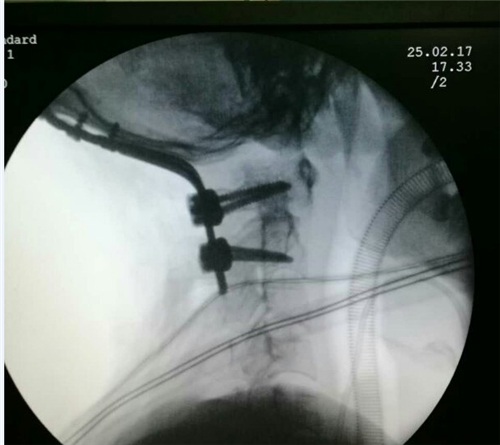

一、德国后路椎间盘镜:德国后路椎间盘镜微创技术在治疗腰椎间盘突出时,将椎间盘镜插入病变腰椎椎板后方,在内镜下将突出的椎间盘摘除。因其可以在纤细的数码内镜指导下完成操作,无须常规手术必要的大切口及较广泛的剥离腰椎周围肌肉、韧带等正常组织,可达到显著的临床治疗效果。